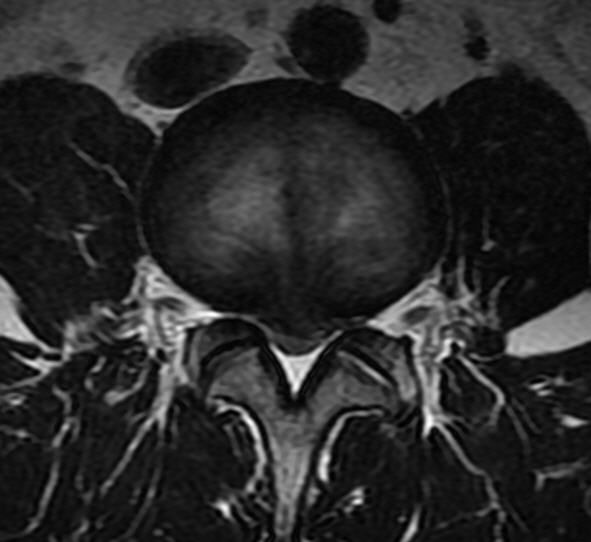

正常椎管

矢径(前后径):13~15mm。

横径(弓根间径):19~29mm (平均24mm)。

临床以矢径确定椎管狭窄

矢径 ‹ 13mm。

横径 ‹ 18mm。

矢径 ‹ 10mm为绝对狭窄。

L1~2(圆形)

L3~4(三角形)

L5(三叶形)